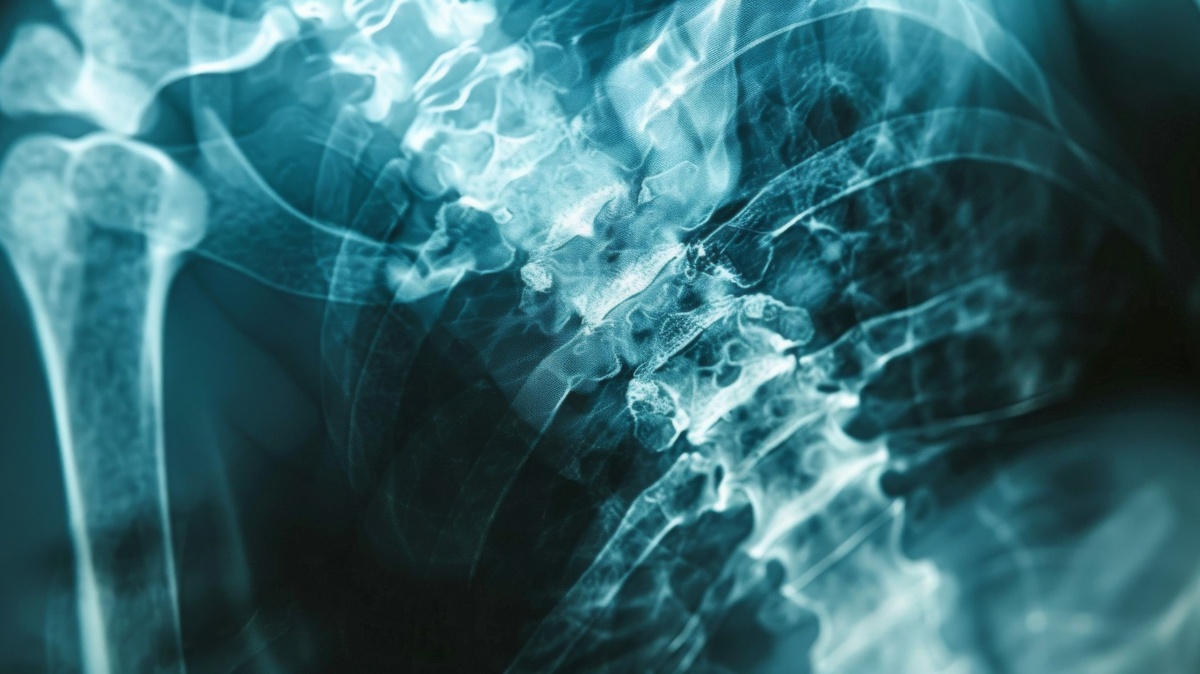

Установлена взаимосвязь между уровнем щелочной фосфатазы и риском развития остеопороза. Регулярное определение этого показателя помогало выявить людей, которым может потребоваться дополнительная оценка состояния костной ткани.